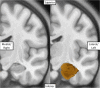

Only recently have more specific circuit-probing techniques become available to inform previous reports implicating the rodent hippocampus in orexigenic appetitive processing1-4. This function has been reported to be mediated at least in part by lateral hypothalamic inputs, including those involving orexigenic lateral hypothalamic neuropeptides, such as melanin-concentrating hormone5,6. This circuit, however, remains elusive in humans. Here we combine tractography, intracranial electrophysiology, cortico-subcortical evoked potentials, and brain-clearing 3D histology to identify an orexigenic circuit involving the lateral hypothalamus and converging in a hippocampal subregion. We found that low-frequency power is modulated by sweet-fat food cues, and this modulation was specific to the dorsolateral hippocampus. Structural and functional analyses of this circuit in a human cohort exhibiting dysregulated eating behaviour revealed connectivity that was inversely related to body mass index. Collectively, this multimodal approach describes an orexigenic subnetwork within the human hippocampus implicated in obesity and related eating disorders.